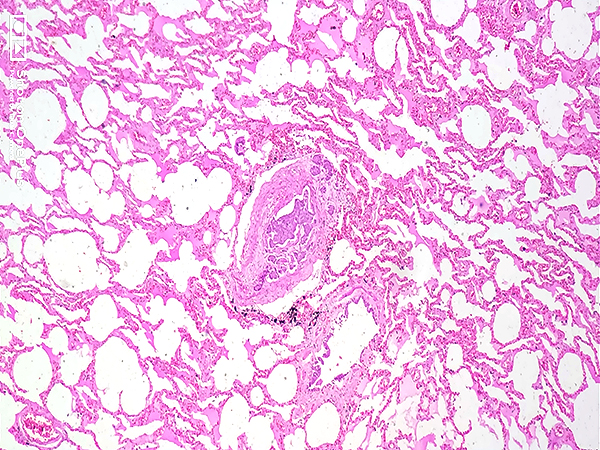

Clinical History:A 55-year-old post-menopausal woman was admitted in respiratory distress and expired within three hours. She had a three-year history of treated hypertension. She endorsed increasing shortness of breath, giddiness and easy fatigability for the preceding month. A previous echocardiograph had been normal and computed tomography (CT) revealed a bulky cervix with hydrometra, left mild hydronephrosis, retroperitoneal / bilateral iliac lymphadenopathy, sclerotic lesions in the lower lumbar vertebrae, and passive venous congestion of the liver. She was treated only symptomatically with bronchodilators. A complete autopsy was performed. Sections from the lung (Figures 1-4) and liver (Fig 5) are shown. Figure 6 is a gross photograph of the uterus and cervix.

The characteristic histopathological findings of PTTM are widespread, microscopic non-occlusive tumor emboli in the pulmonary arterioles, fibrocellular and/or fibromuscular intimal proliferation, and secondary thrombosis due to localized activation of coagulation pathways leading to luminal stenosis. The sequelae include sub-acute respiratory failure, pulmonary hypertension, right-sided heart failure, and sudden death. The fatality rate is high and it is a challenging ante-mortem diagnosis.

In the present case, sections from the lung showed tumor emboli, fibrin deposition, organized thrombi with recanalization, and fibrocellular intimal proliferation in the small pulmonary arteries. Sections from the liver showed tumor emboli in the portal vein radicle and the hepatic sinusoids. The malignant cells were squamoid with abundant eosinophilic cytoplasm and large vesicular nuclei. An endophytic tumor was identified in the cervix. The adjacent wall appeared thickened and trabeculated. Microscopically it was identified as a squamous cell carcinoma and numerous lymphovascular emboli were noted. The other organs were unremarkable. Based on these findings, the tumor emboli in the lung and liver were thought to originate from the primary tumor in the cervix.